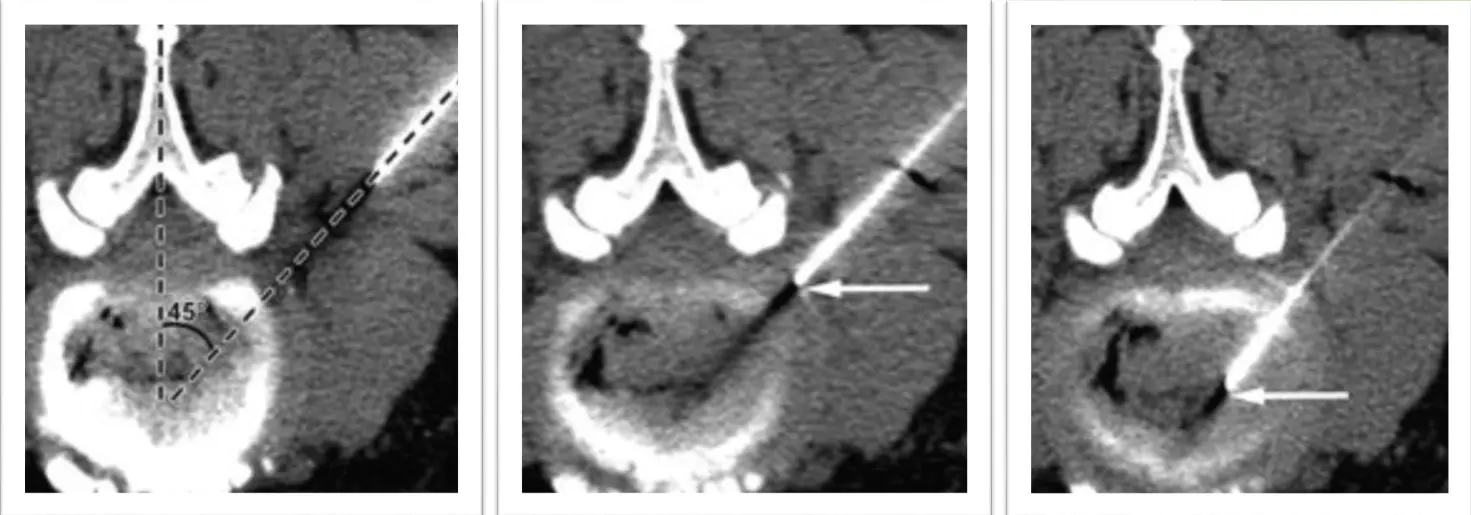

1 Určenie miesta vpichu pomocou CT scanov, dezinfekcia a zavedenie Chiba ihly.

2 Kontrola polohy ihly CT scanmi až k cieľovému koreňu/kĺbu.

3 Aplikácia liečebnej zmesi: 1 ml kontrastnej látky, 4 ml Marcainu (anestetikum) a 1 ml Diprophosu (kortikoid).